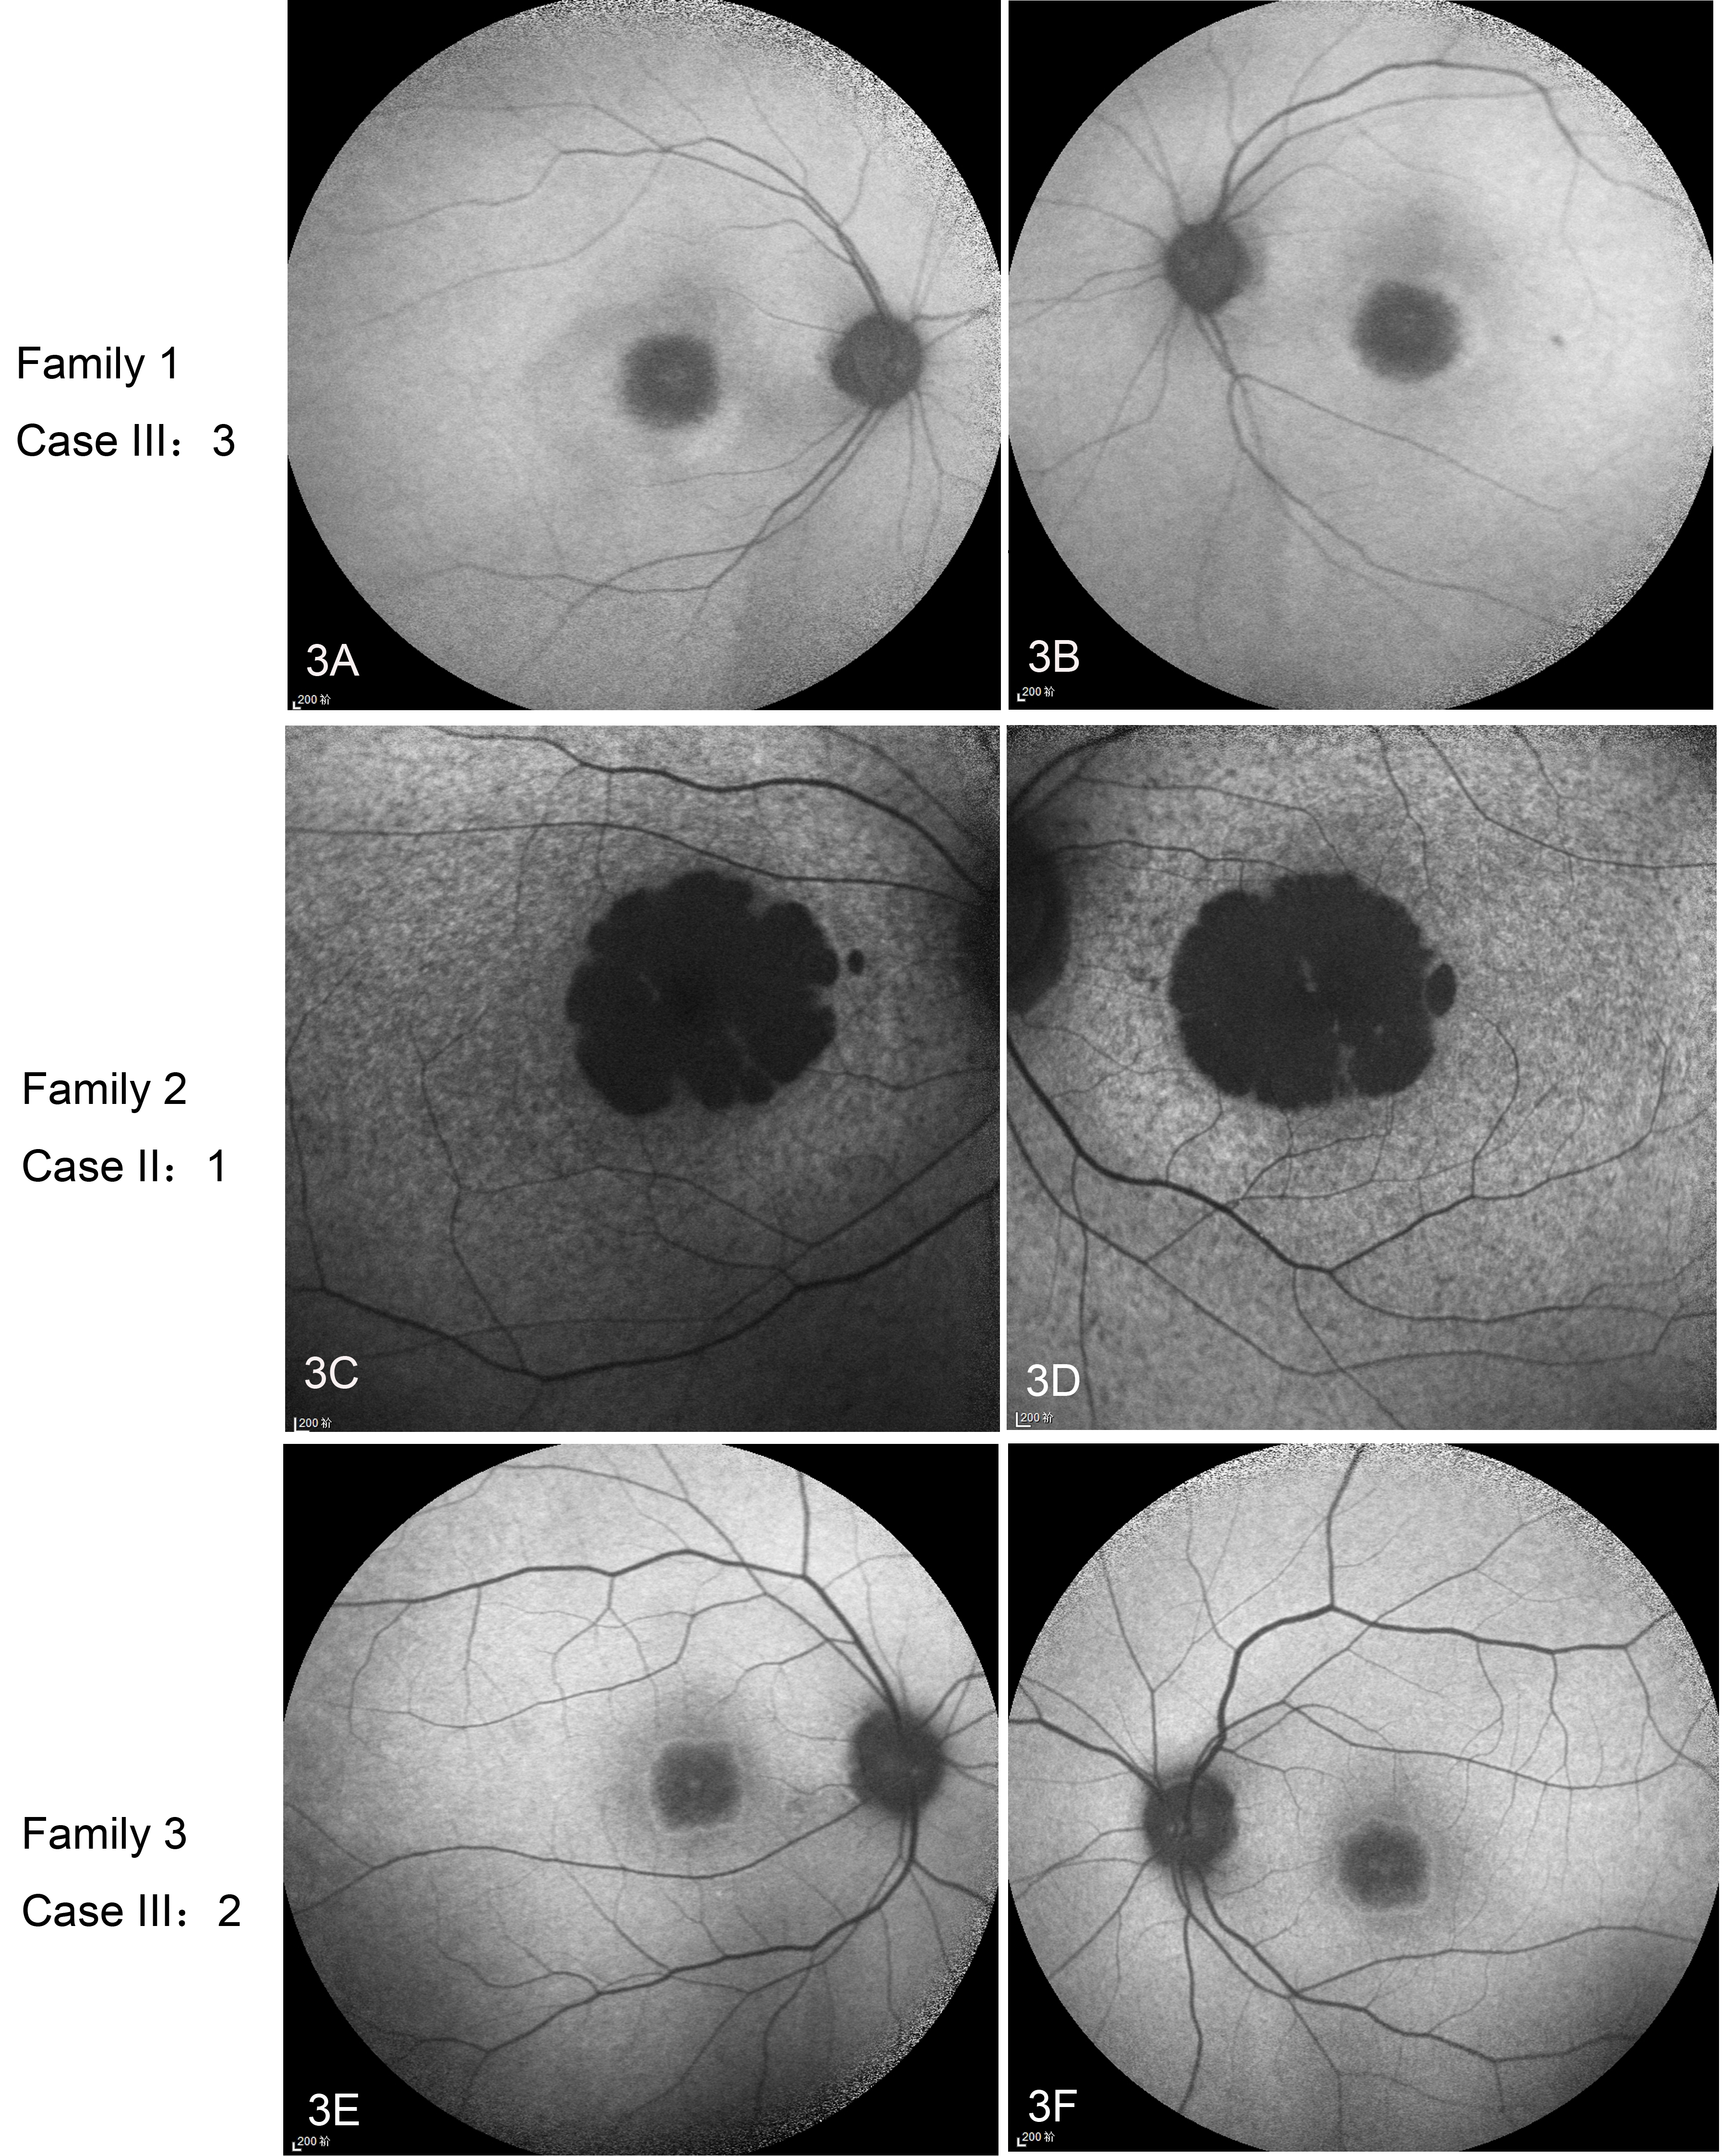

Figure 3. AF in patients with variants in AXTN7. A, B: Family 1 Case III:3 is a 54-year-old woman. Autofluorescence (AF) shows a hypofluorescence patch in the macular area with

a surrounding hyperfluorescent ring. C, D: AF was taken during the second visit of Family 2 Case II:1 when she was 18 years old. AF shows a dark macula and mottled

fluorescence in the posterior pole. E, F. Family 3 Case III:2 is a 32-year-old man. AF shows a hypofluorescence patch in the macular area with a surrounding hyperfluorescent

ring.